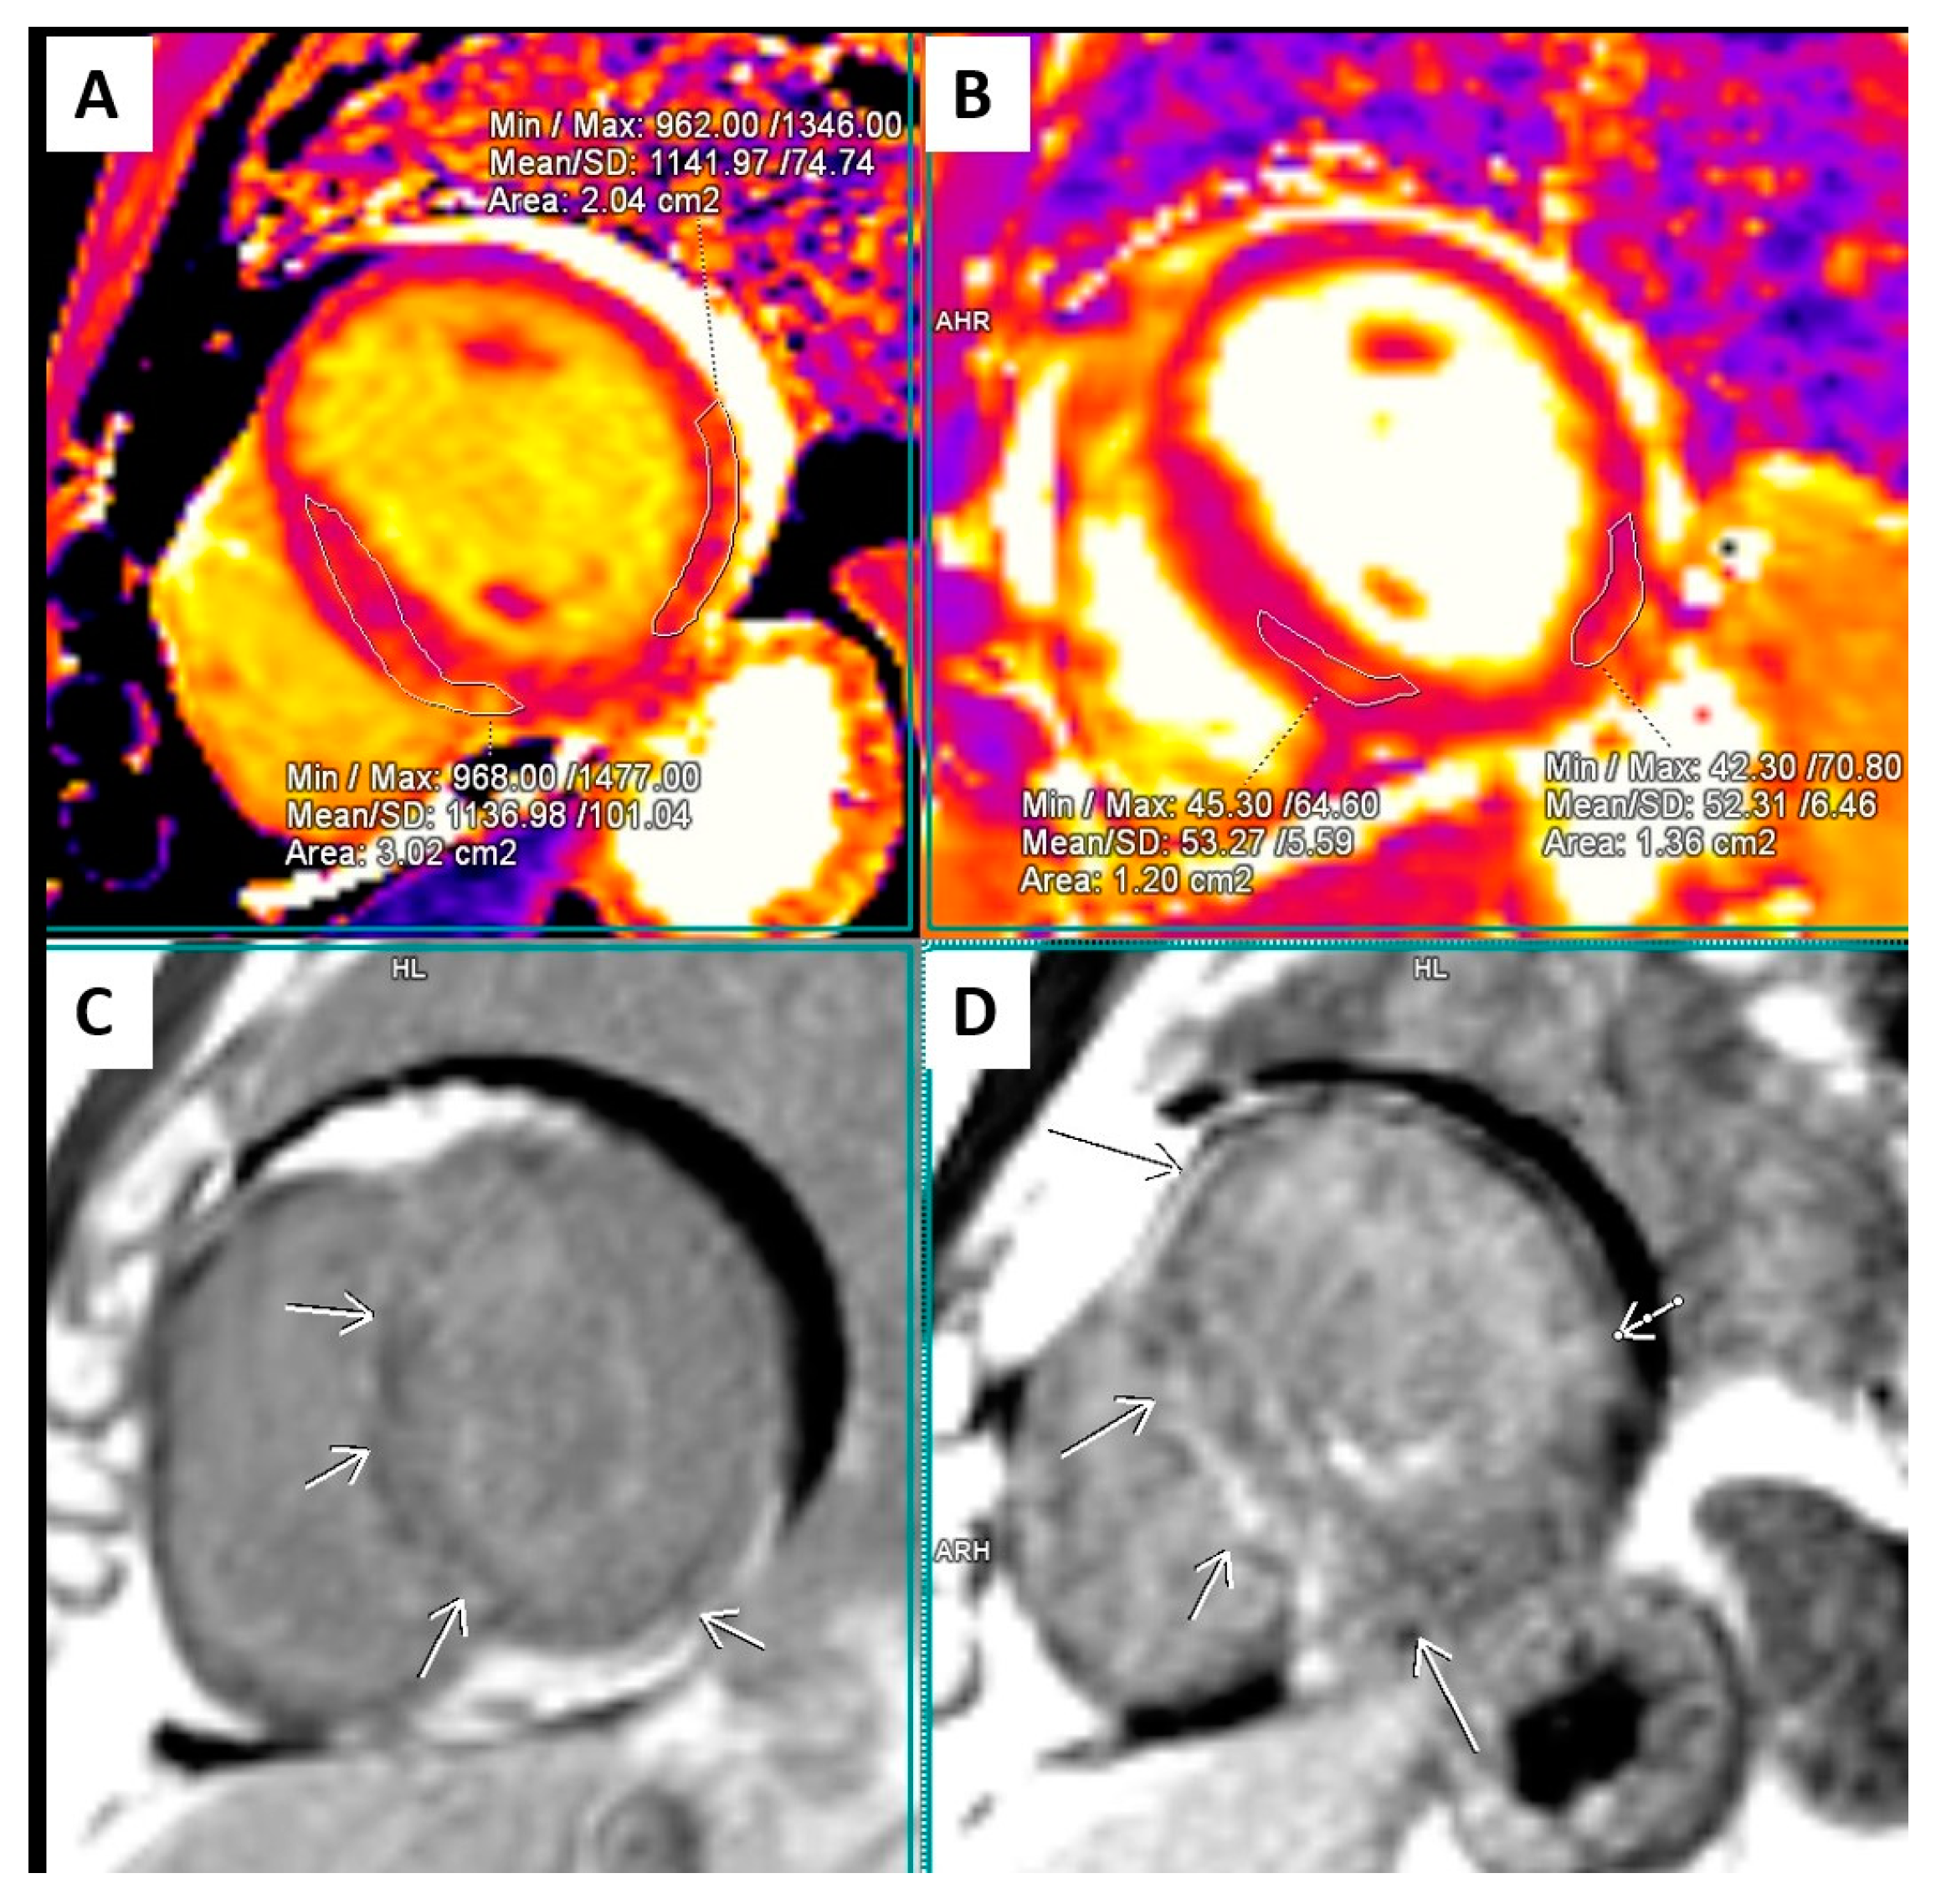

2.2. Cardiac Magnetic Resonance (CMR)

| March 2021, age 45 | First episode of decompensated heart failure, NYHA III-IV class; A new episode of persistent AF, duration longer than two months | Management of failure according to guidelines; TEE not performed due to INR not being in target; Asymmetric left ventricular hypertrophy and reduced ejection fraction noted; Further diagnostic work-up recommended—cardiac magnetic resonance (CMR) and genetic testing; Test for Anderson–Fabry disease—negative; CMR study positive for cardiomyopathy with diffuse fibrosis, possibly hypertrophic or infiltrative.  | At admission: Amiodarone 400 mg; Torasemide 20 mg; Irbesartan 75 mg; Acenocoumarol; At discharge: Torasemide 50 mg; Spironolactone 50 mg; Acenocoumarol; Bisoprolol 5 mg; Sacubitril/valsartan 2 × 24/26 mg; Allopurinol 150 mg; Dapagliflozin 10 mg  |